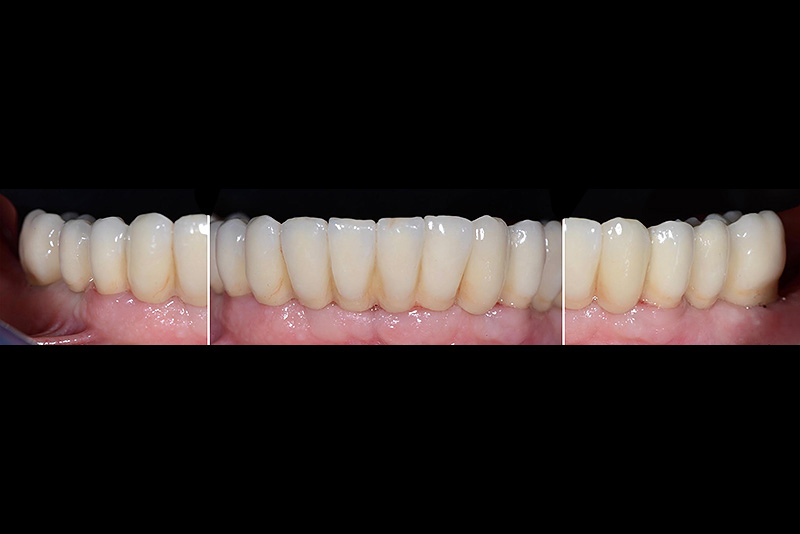

Vengono utilizzati 2 tipi di provvisori: il primo, cementato ai denti vicini, viene utilizzato dal momento dell’estrazione del dente fino ad impianto osteointegrato (circa 6 mesi); il secondo, avvitato direttamente all’impianto, ha una funzione di prova estetica ma soprattutto di guida per la maturazione dei tessuti gengivali peri-implantari portandoli verso la maturazione completa prima di posizionare la corona finale in disilicato di litio.